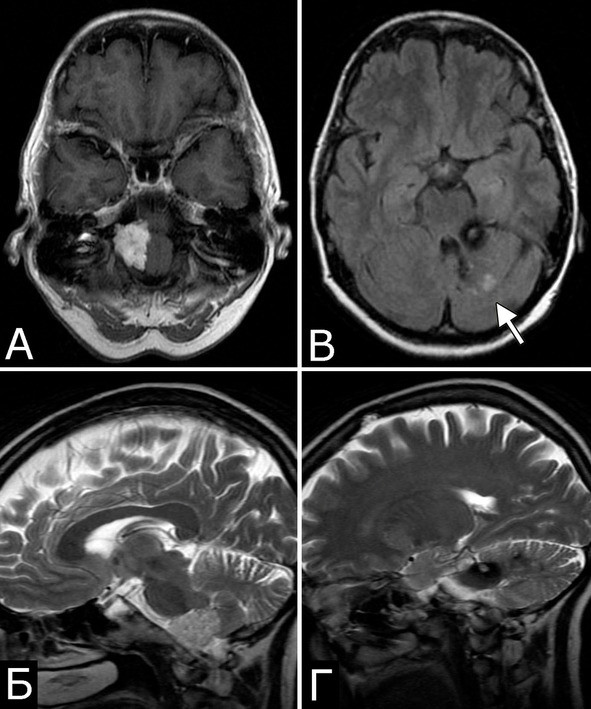

У 6 больных каверномы сочетались с венозными ангиомами и аномалиями венозной системы. Крупные патологические вены, расположенные в непосредственной близости к КМ, часто обнаруживают при МРТ или на операции, в связи с чем многие авторы рассматривают их как единую патологию (28, 93, 154, 351, 357). Тем не менее, в ряде случаев кавернозные и венозные мальформации можно четко дифференцировать как самостоятельные образования, особенно если они находятся в разных отделах мозга. У двух больных патология венозной системы представляла собой аномалию сразу нескольких крупных венозных коллекторов головного мозга (рис. 2).

Рис. 2.Б-ной П, 22 г. Сочетанная сосудистая патология мозга: Множественные КМ головного мозга. Аномалия развития венозной системы мозга. А – КМ височной, теменной и затылочной долей слева (МРТ, режим Т2, аксиальная проекция). Б, В – аномалия развития костей и оболочек мозга в виде локальной деформации внутренней костной пластинки и губчатого вещества теменных костей в области впадения патологической вены в ВСС. Расщепление аномального ВСС на две лакуны, пролабирование мозга в область дефекта (МРТ, режим Т1, сагиттальная и фронтальная проекции). Г – аномалия венозной системы в виде отсутствия прямого синуса, формирования крупной патологической вены, впадающей в заднюю треть ВСС (МРТ-АГ, сагиттальная проекция)